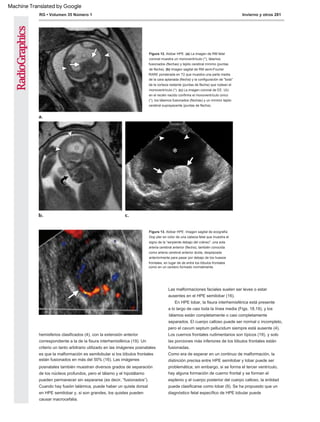

Figura 15. HPE semilobar. (a) La imagen de US coronal muestra un monoventrículo (*) y fusión parcial de los tálamos (T). (b) Imagen coronal de RM semi-Fourier

RARE ponderada en T2 que muestra el parénquima cerebral anterior continuo (flecha), el monoventrículo (*) y los tálamos parcialmente fusionados (T). (c) Imagen

coronal de RM RARE de medio Fourier ponderada en T2 más posteriormente que muestra dos lóbulos occipitales separados por la hoz (flecha).

Figura 14. HPE semilobar. (a) Imagen ecográfica oblicua axial que muestra un manto continuo de cerebro en la

parte anterior (puntas de flecha) pero en la parte posterior con división en hemisferios (flechas). (b) Una imagen de

US axial más inferior en el mismo paciente muestra estructuras normales de la fosa posterior (flecha) debajo de la

tienda del cerebelo pero fusión del cerebro supratentorial anterior (puntas de flecha).

Figura 18. HPE lobar. (a) La imagen axial de US muestra un eco continuo en la línea media anteriormente (flecha). No pudimos demostrar el cavum

septum pellucidum en ningún plano. (b) La imagen de RM fetal axial muestra una división aparentemente completa de los hemisferios cerebrales

(puntas de flecha). (c) La imagen de RM fetal coronal muestra la continuidad del giro anteroinferior entre los lóbulos frontales (flecha). Esto no fue

demostrable en EE.UU.; el hallazgo índice fue la incapacidad para demostrar un cavum septum pellucidum normal.

Figura 19. HPE lobar. (a) La imagen de RM fetal muestra la continuidad de los lóbulos frontales a lo largo de la línea

media (flecha), la presencia del cuerpo calloso (punta de flecha) y la ausencia del cavum septum pellucidum. (b) La

imagen de US coronal posnatal muestra fusión de los lóbulos frontales anteriores (*) con interdigitación de surcos a lo

largo de la línea media (flechas).